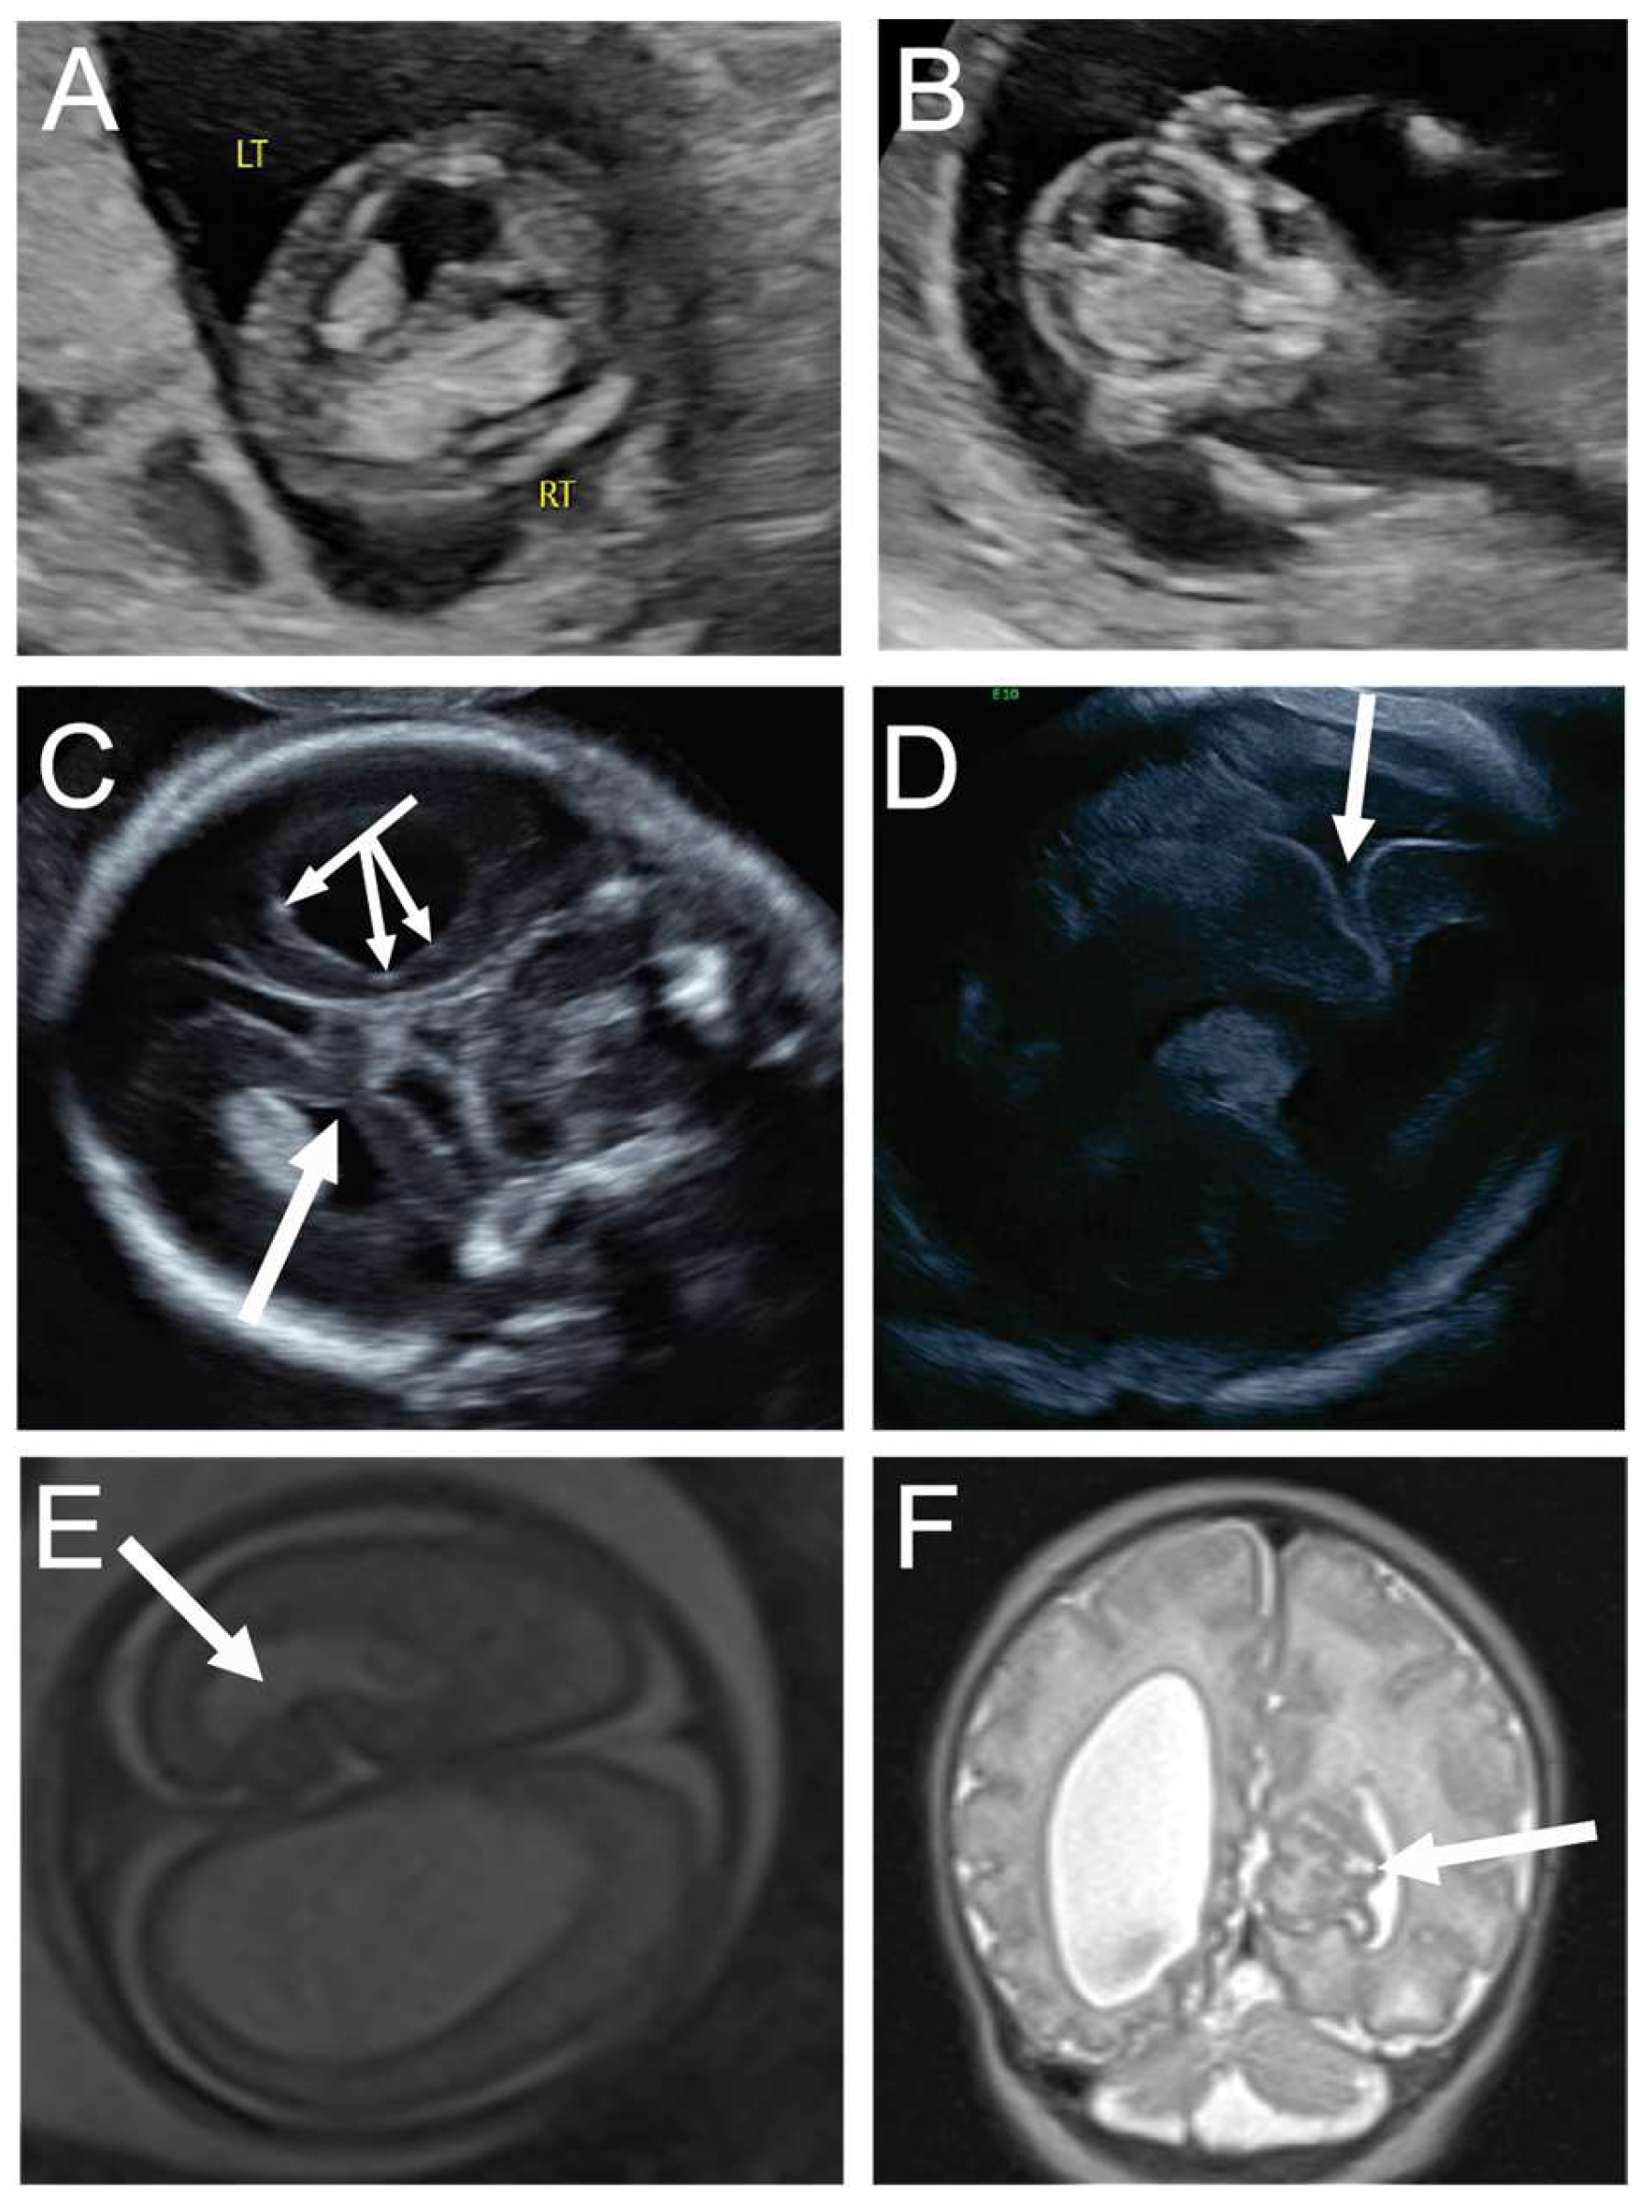

A 31-year-old G3P1 at 13 weeks and 1 day’s gestation was seen for first-trimester screening, and the fetus was noted to have an irregular, asymmetrically enlarged and mottled right choroid plexus, concerning for possible early right intraventricular hemorrhage and ventriculomegaly, note Rt = right side of fetus and Lt = left side of fetus (A,B). Maternal serum infectious and neonatal alloimmune thrombocytopenia workups were negative. Neurosonogram at 20 weeks and 0 days demonstrated the same severe unilateral right ventriculomegaly with stippling along the lining of the right ventricle, consistent with germinal matrix hemorrhage versus heterotopia (triple headed arrow, (C)), with additional findings of right periventricular white matter loss and a contralateral focal area of abnormal folding of the left mesial cortex, concerning for cortical dysplasia or polymicrogyria (single arrow, (C)). Fetal MRI confirmed right unilateral ventriculomegaly with evidence of right germinal matrix and intraventricular hemorrhage, as well as cortical abnormality in the left mesial occipital lobe (arrow, (E)). The mother opted to continue the pregnancy and declined amniocentesis. Ultrasound at 26 weeks and 5 days’ gestation showed progressive right ventriculomegaly with midline shift and continued prominence of contralateral cortical dysplasia, with possible progression to schizencephaly (arrow, (D)). She was delivered via cesarean at 36 weeks in the setting of preterm labor. Postnatal MRI demonstrated worsening of the cortical maldevelopment in the left mesial occipital lobe (arrow, (F)), a few scattered foci of periventricular nodular heterotropia, and abnormal vertical and shallow appearance of the right sylvian fissure. At two years of age, the child was meeting developmental milestones.